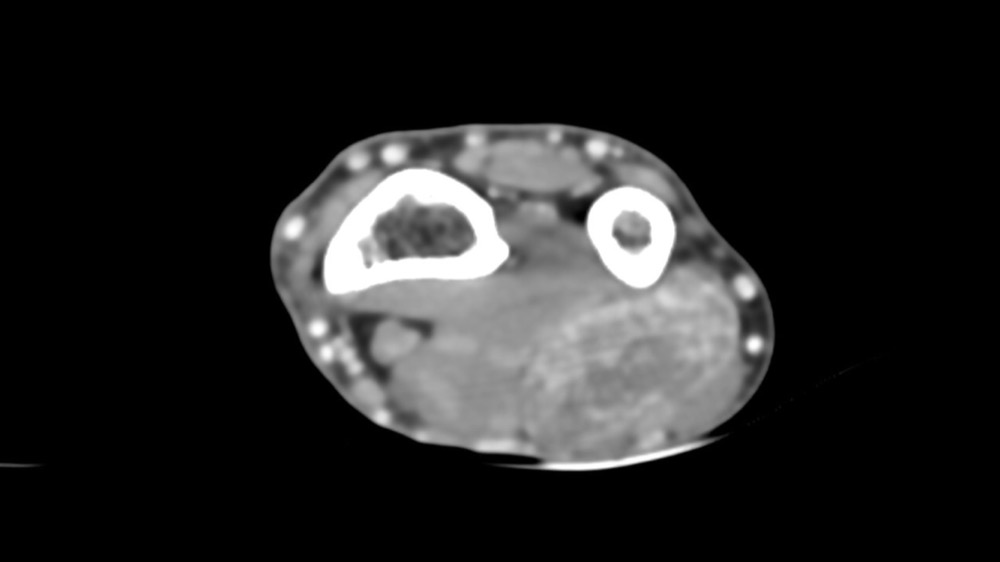

Bone Club

Thomas Leclerc 23/03/2022